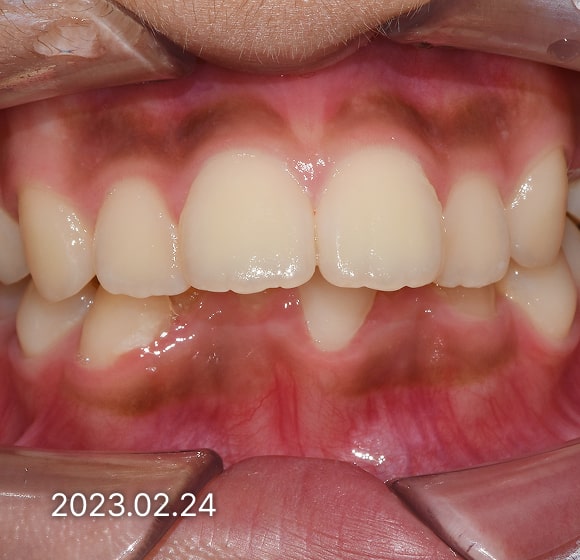

BEFORE / AFTER

전후 변화로 보는 치료사례

본 사진은 진심을담은치과교정과 치과의원에서

치료한 환자의 동일 인물 전·후 사진입니다.

개인의 구강 상태 및 관리 방법에 따라 통증 및 잇몸 염증,

턱관절 불편감 등의 부작용이 발생할 수 있습니다.

치료 전 치료 후

덧니, 삐뚤한 치열